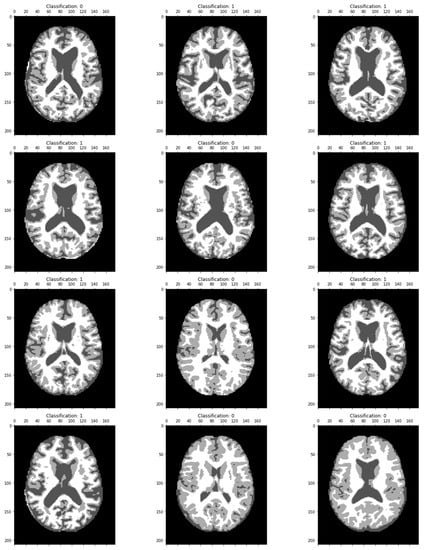

The proposed work aims at the early detection of AD. The data sets play an important role as the training data is needed to train the model for performing the needed actions. Most of the data in the data set used for training the model and data set is also separated into test data. The proposed system executes the algorithm on AD-related datasets obtained from Kaggle with 512 MRI images and the Munich database with 112 PET images; Figure 3 and Figure 4 show the sample image data.

Figure 4.

Sample PET scan image showing an Alzheimer’s affected brain. Noted is the size of the enlarged ventricles.

The MRI image classified results are displayed in Figure 7. Dementia has been classified in each image as a particular region.

Figure 7.

MRI image classification results showing the classification value as 0, confirming the absence of Alzheimer’s disease, and Classification 1 shows the brain image of an Alzheimer-affected person.